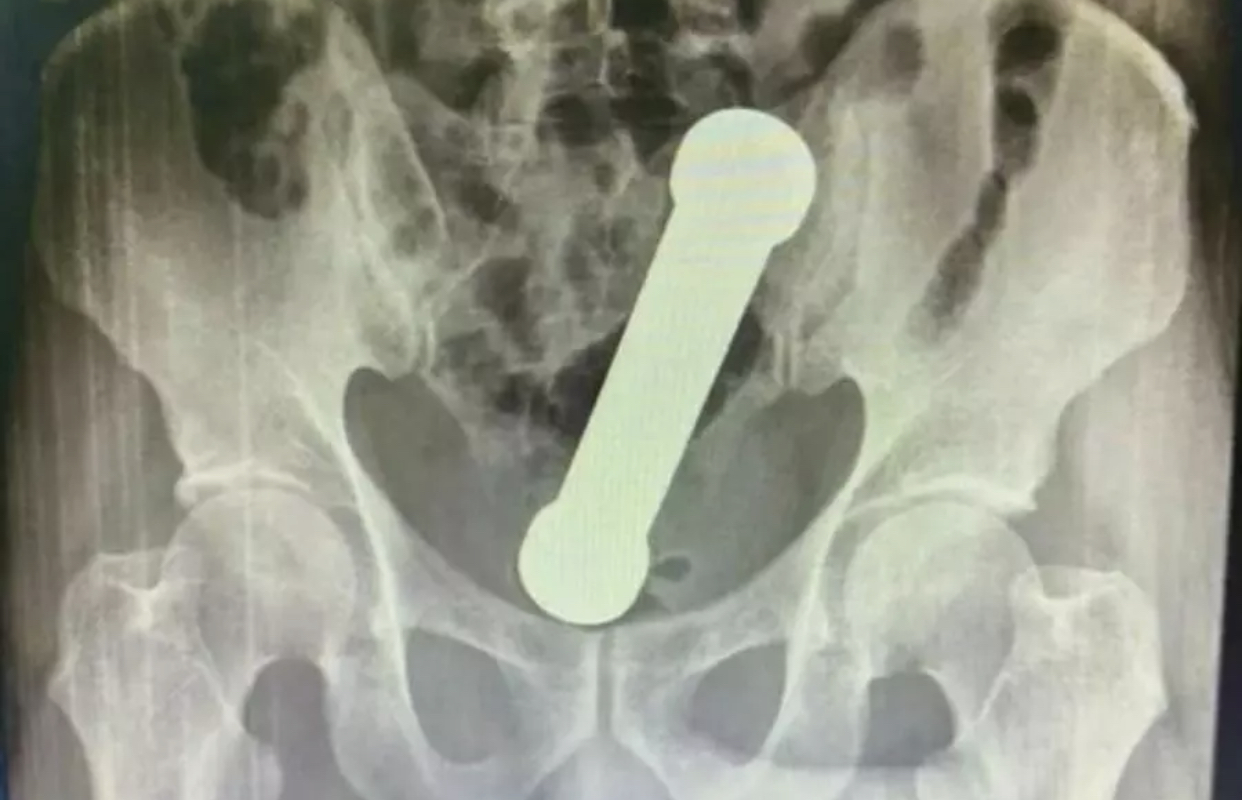

Ao realizarem um exame de raio-X, os médicos encontraram um peso de dois quilos, de cerca de 20 centímetros de comprimento, como os que são usados em academias de ginástica para exercícios de braço, dentro do homem. O haltere estava entre o reto e o intestino grosso do paciente, que, depois do exame, admitiu ter introduzido o peso de academia no corpo para obter satisfação sexual.